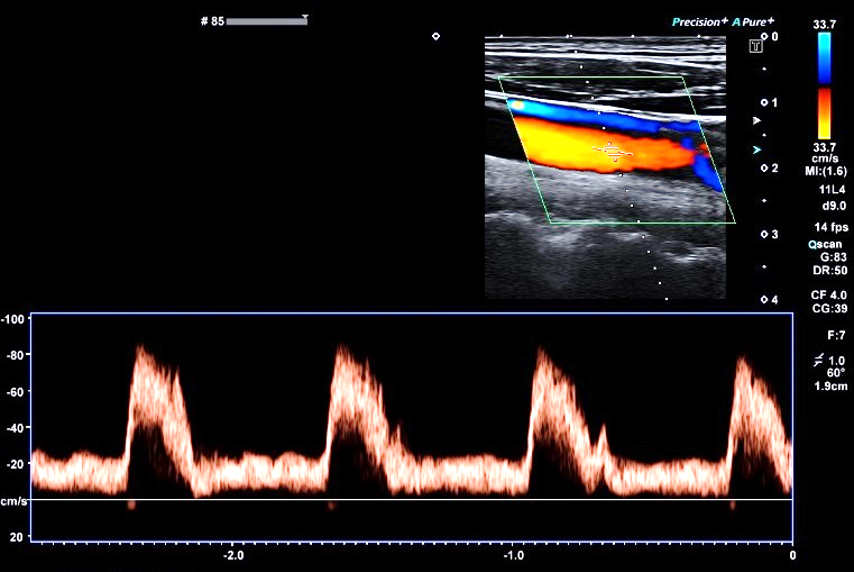

頚動脈エコー

頚動脈は、頚の部分にあり、心臓から脳へ血液を送る大きな血管のことです。頚動脈は脳へ血液を送る「内頚動脈」と、頭皮の方へ血液を送る「外頚動脈」とがあり、それら分かれ道となる部分を『頚動脈分岐部』といい、もっとも「動脈硬化」になりやすい部位といわれています。

頚動脈エコー検査では、頚動脈の状態を超音波によって検査するので、心筋梗塞や脳梗塞、大動脈解離などの命にかかわる病気が発症する危険度を事前に知ることができます。頚動脈エコー検査で頚動脈の動脈硬化(老化も含む)やアテローム硬化の状態を観察できます。